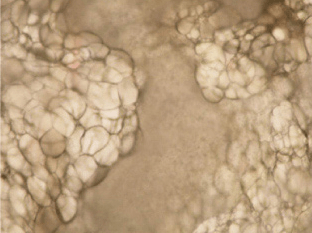

脂肪细胞呈现为均匀细小的泡状。

被溶解的区域开始出现并扩散开来。 周围的血管不受影响,血液的流动得以保证。

脂肪细胞的细胞膜破裂,存在于被称作油滴的储藏库中的中性脂肪,随着时间的推移被溶解出来,并随着血液或淋巴系统排出,或者作为能量被消耗掉。